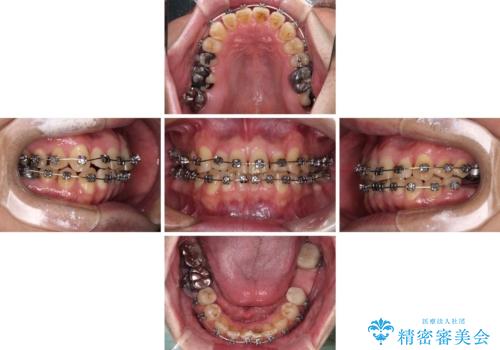

ここまでの治療を提案したところで、折角なのでしっかり治療を行いたいとのことで、前歯のデコボコやクロスバイトを改善するための矯正治療を行うこととしました。

まずは奥歯の痛みを改善し、その後矯正治療を行い、最後にオールセラミックブリッジによる補綴治療を行うこととしました。

むし歯をきっかけに矯正治療を行うこととなりましたが、学生の頃から気になっていた歯列を改善することができ、患者様には大変満足していただけました。